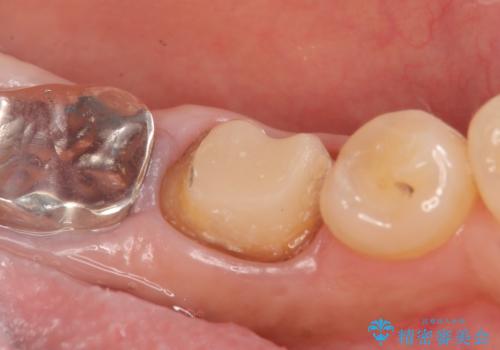

- 左下の銀歯が外れたので診て欲しいといらっしゃった方の症例です。

他院にて再装着したが不安なので、根管治療からやり直したいとのことでした。

再根管治療終了後、オールセラミッククラウンによる補綴を行いました。